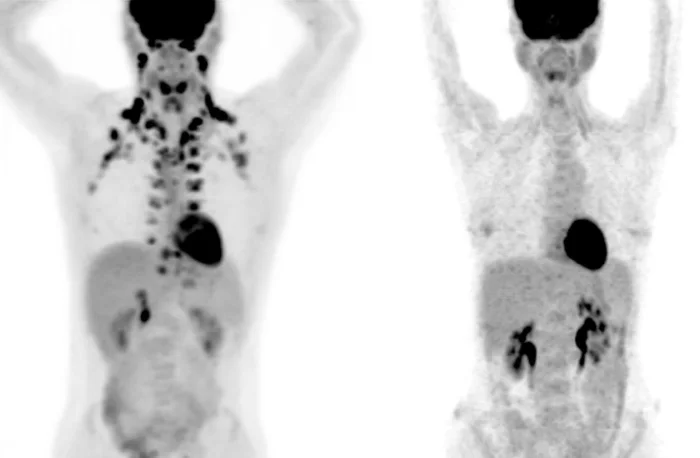

Дело в том, что изучение бурого жира — сложная задача, так как эта ткань выявляется только на ПЭТ-сканировании, специальном виде медицинской визуализации. «Эти снимки дорогие, но, что более важно, они используют радиацию«, — говорит Тобиас Бехер, первый автор исследования. «Мы не хотим подвергать этому многих здоровых людей«.

Благодаря этой «базе данных», исследователи исследовали 130 000 ПЭТ-сканирований более 52 000 пациентов, выявив наличие бурого жира примерно у 10% людей. Затем они указали, что некоторые общие и хронические заболевания реже встречаются у этих же людей. Например, только 4,6% из них страдали диабетом 2 типа по сравнению с 9,5% у остальных. Точно так же у 18,9% развился аномальный холестерин по сравнению с 22,2% у тех, чей бурый жир не определялся.